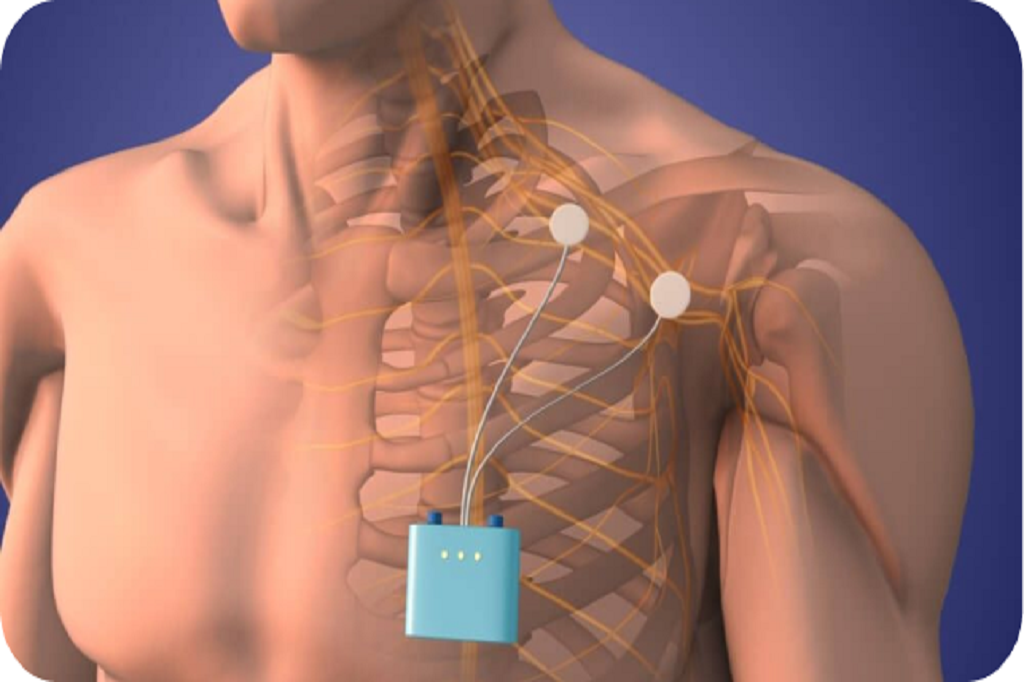

A diagnostic block or temporary "bridge" therapy for shoulder or hip nerve pain.